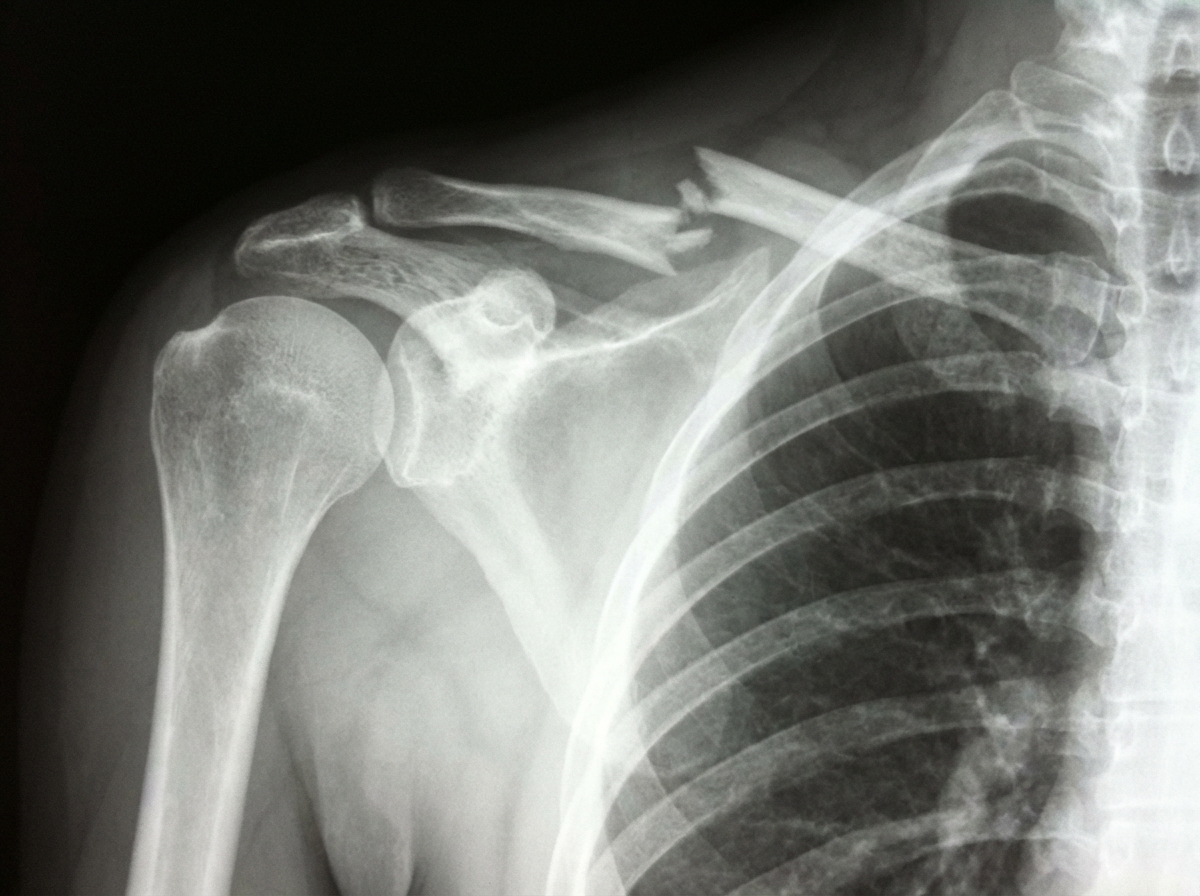

What is the finding seen on X-ray of the right shoulder?

Explanation: ***Fracture of the clavicle*** - **Clavicle fractures** are the most common shoulder injuries, typically showing a clear **discontinuity** of the cortical bone with possible **displacement** or **angulation**. - On X-ray, look for **cortical disruption**, **bone fragment overlap**, or **step-off deformity** along the clavicular shaft, most commonly in the **middle third**. *Fracture of the scapula* - Scapular fractures are **uncommon** and require significant **high-energy trauma**, typically from motor vehicle accidents or falls from height. - X-ray would show **cortical breaks** in the scapular body, neck, or glenoid, often requiring **CT scan** for detailed evaluation due to overlapping structures. *Fracture-dislocation of the acromioclavicular joint* - AC joint injuries present with **widening** of the **acromioclavicular space** and possible **superior displacement** of the clavicle relative to the acromion. - Associated with **coracoclavicular ligament disruption**, showing increased **coracoclavicular distance** on X-ray, not a discrete bone fracture. *Fracture of the 1st rib* - First rib fractures are **extremely rare** and typically associated with **severe thoracic trauma** or **neurogenic thoracic outlet syndrome**. - Would appear as a **cortical break** in the **curved first rib** near the thoracic apex, often requiring **dedicated rib views** or **CT** for visualization.